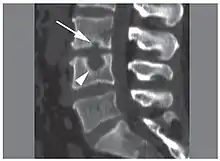

![]() | |

| X-ray image of Schmorl's nodes in the lumbar spine | |

Schmorl's nodes can be detected with X-rays, although they can be imaged better by CT or MRI. They are considered to be vertical disc herniations through the cartilaginous vertebral body endplates. Schmorl's nodes can sometimes be seen radiographically, however they are more often seen on MRI, even when not visible on plain X-rays. They may or may not be symptomatic, and their etiological significance for back pain is controversial. In a study in Spine by Hamanishi, et al., Schmorl's nodes were observed on MRI in 19% of 400 patients with back pain, and in only 9% of an asymptomatic control group. The authors concluded that Schmorl's nodes are areas of "vertical disc herniation" through areas of weakness in the endplate.[5]